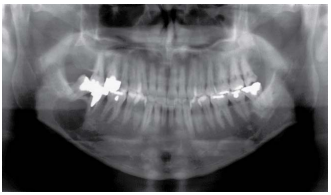

A radiografia panorâmica abaixo mostra uma radiolucência unilocular associada ao espaço periodontal do segundo molar inferior direito. Enunciado 3586303-1

O aspecto radiográfico da região mencionada é sugestivo de: